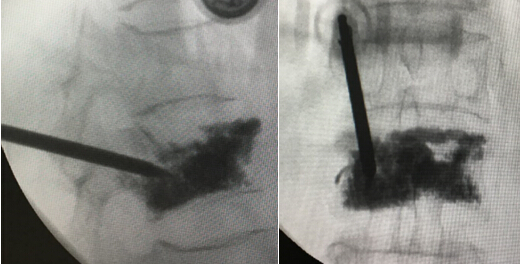

术中透视L1椎体骨水泥分布满意,无明显渗漏